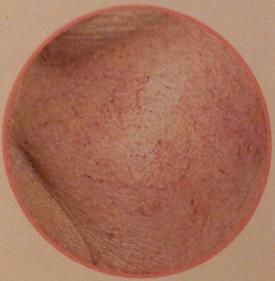

Cuperosis: En una eritrosis establecida, algunos vasos están más dilatados que otros y hasta pueden verse a simple vista. Estos pequeños vasos rojos (telangiectasias) constituyen la cuperosis.

Rosácea

La rosácea antes recibía el nombre de “acné rosácea” porque, además de eritrocuperosis, aparecen pústulas (granitos) parecidos a las del acné vulgar.